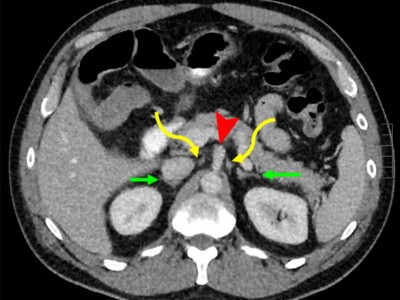

ECR26 / C-10070

Beyond the mass: differentiating retroperitoneal fibrosis from malignancy and other retroperitoneal pathologies M. Gorjón Gómez, C. Jiménez Relimpio, E. Casado Lorente, B. Alonso Márquez, E. Mira Figueroa Sánchez, M. Morena López, S. R. Vallejo Rivera, P. Beneitez Mascaraque, L. Nicolás Liza; Guadalajara/ES -